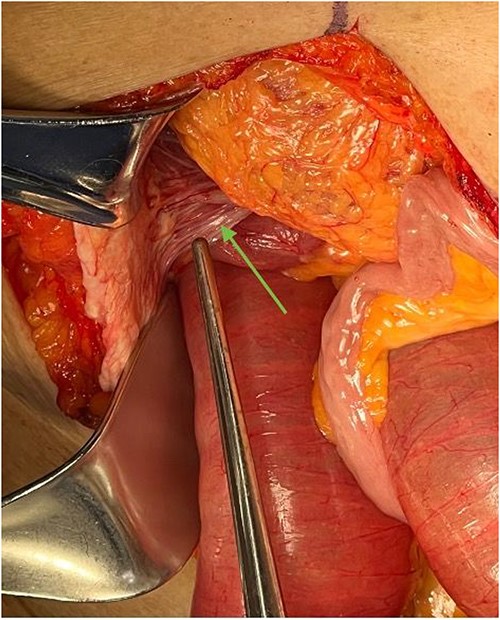

The small intestines proximal to the midgut volvulus was dilated. The small intestines distal to the volvulus and Ladd's bands was decompressed (Fig. 3).

Dilated loops of small bowel proximal to obstruction and collapsed bowel distal to the obstruction.